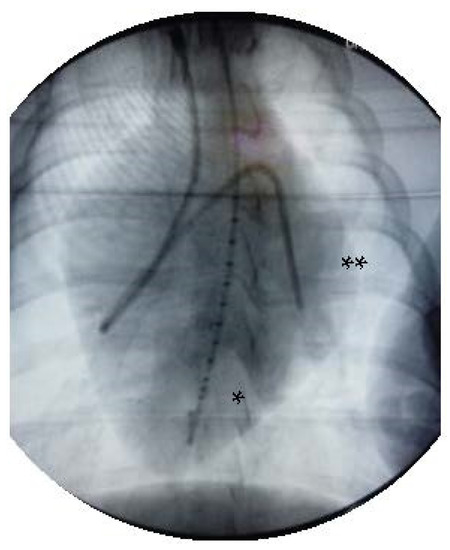

2.1. Experimental Setup